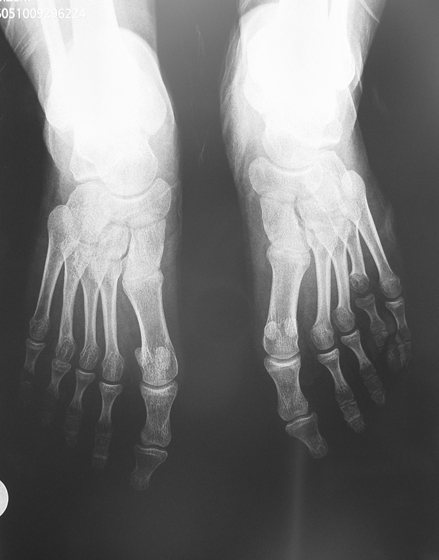

Vaka 3